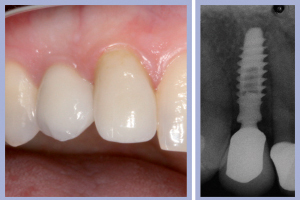

- Figg. 29a, b Manufatti di destra e radiografia di controllo. Si noti l’ottima integrazione tissutale

La valutazione clinica al momento della consegna dei manufatti e clinico-radiologica a 3 mesi dalla consegna manifestava una completa integrazione tissutale con eccellente recupero estetico e funzionale (Figg. 29-30).